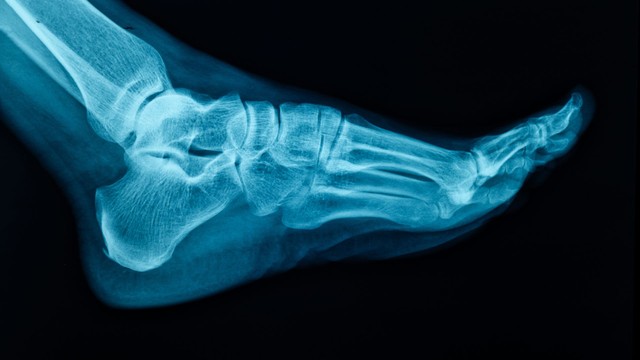

X quang